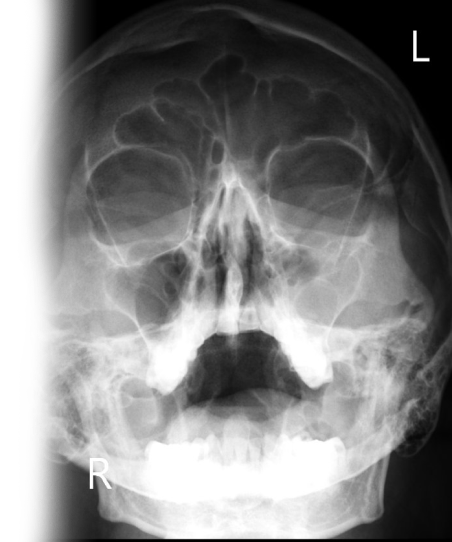

Рентгенография придаточных пазух носа

Рентгенография придаточных пазух носа – важный метод обзорного исследования состояния придаточных пазух носа.

Диагностическая услуга выполняется в одной проекции.

• подозрение на наличие патологии придаточных пазух носа: заложенность носа, головные боли, зеленое отделяемое, частые рецидивирующие воспалительные заболевания пазух;

• для исключения в пазухах острого или хронического воспалительного процесса, наличия кист, полипов, оценки развития системы придаточных синусов носа;

• рентгенография также позволяет оценить положение носовой перегородки.